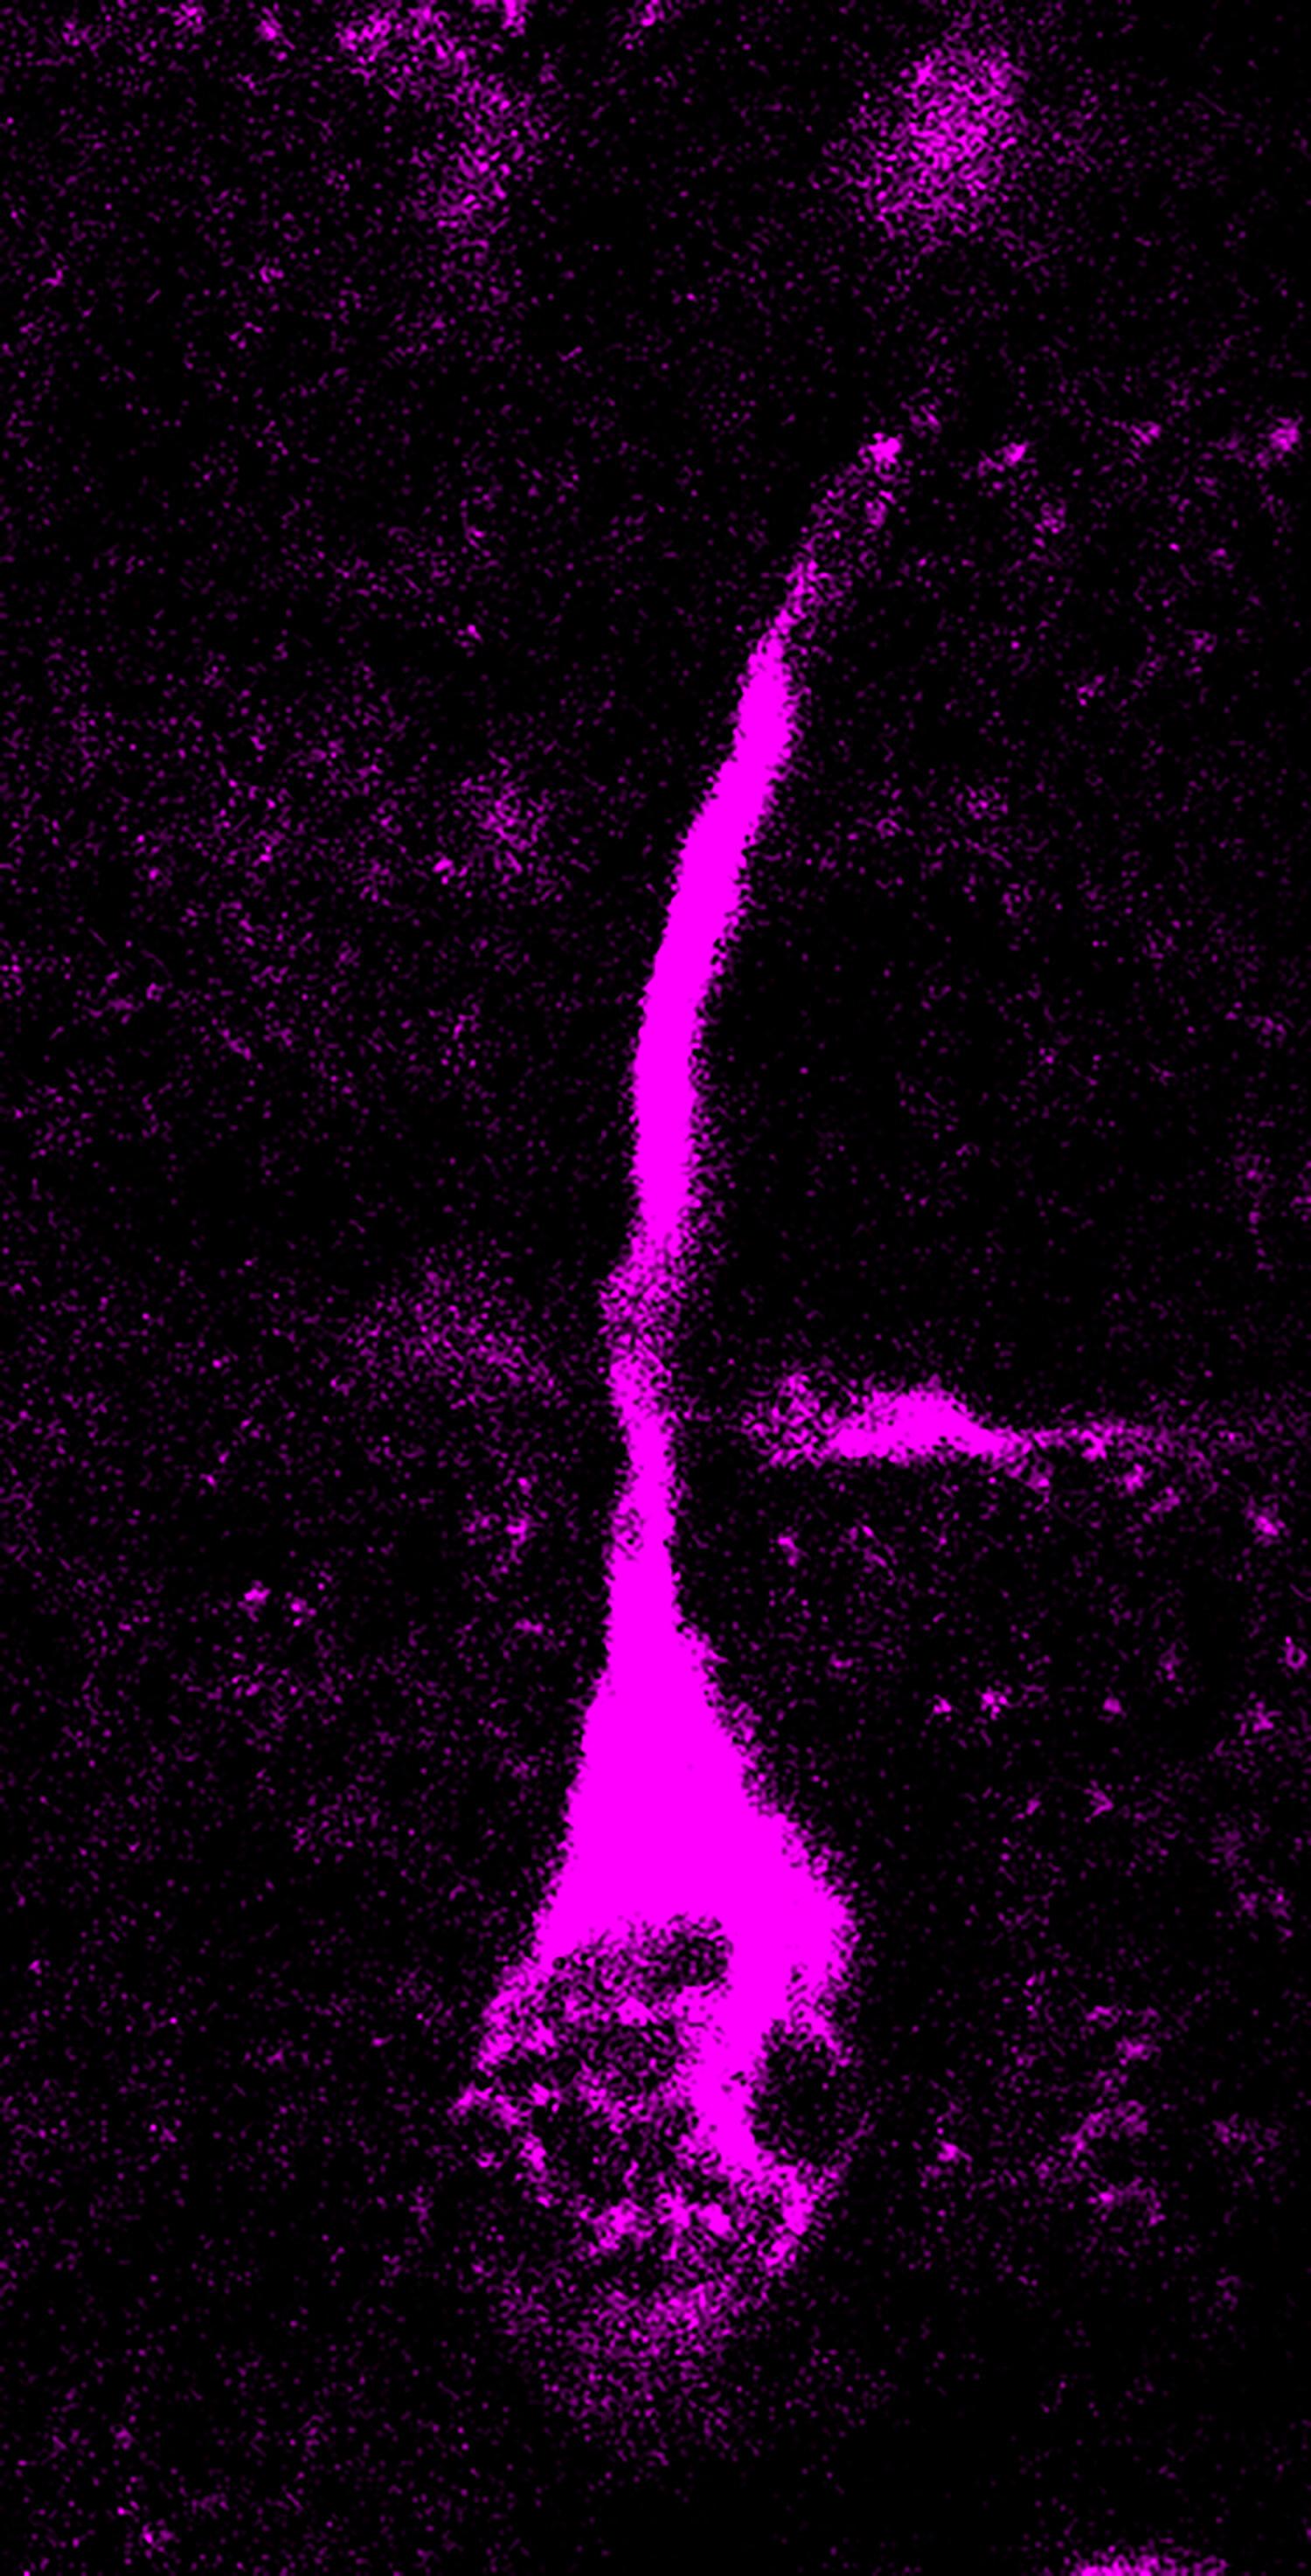

与尼安德特人相比 人类TKTL1意味着现代人额叶新皮层的神经发生更大(Credit: Pinson et al., Science 2022 / MPI-CBG)

Anneline Pinson和同事将现代人与尼安德特人以及其它猿类的基因组序列进行比对后发现,现代人体内存在一个独特的由TKTL1基因编码的氨基酸替换。当被置于类器官中或在小鼠和雪貂脑中进行过度表达时,Pinson等人发现,人类TKTL1变体(hTKTL1)会比古人类变体产生更多的基底放射状胶质(bRG)神经母细胞,进而导致新皮层神经元增殖。在人类胎儿新皮层组织和大脑类器官中破坏hTKTL1的表达或用古人类变体替换hTKTL1则会导致bRG和神经元生成减少。